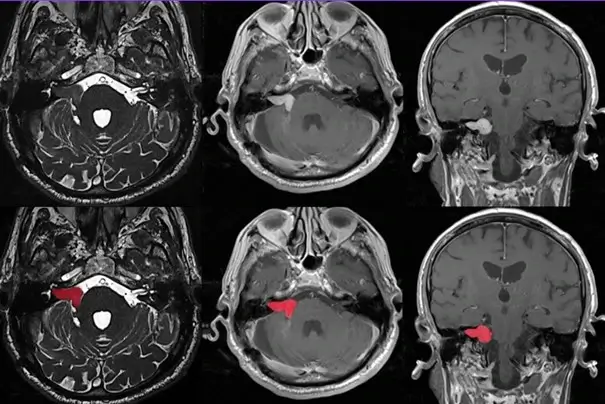

Néanmoins un stade est souvent atteint auquel des symptômes se font ressentir ; en général une baisse d’audition, on parle de surdité de perception unilatérale progressive. Cela mène à des tests ORL, une audiométrie, et surtout une IRM permettant de poser le diagnostic médical. Parfois ces symptômes apparaissent brutalement avec des vertiges, instabilités, acouphènes, sensation de pression ou d’oreille pleine, et même des faiblesses au visage témoignant d’une contrainte sur le nerf facial passant par cette zone.

Le traitement dépend des symptômes, et essentiellement du volume de la tumeur et de l’évolution de ce dernier. En effet, plus le volume est important et handicapant, plus la chirurgie sera proposée. A l’inverse, les plus petits schwannomes vestibulaires, sans troubles ressentis, ne recevront même pas de traitement et seront suivis par IRM. Ainsi plusieurs classifications ont été élaborées pour quantifier ce volume, ainsi que le rapport de ce dernier vis-à-vis des structures environnantes.